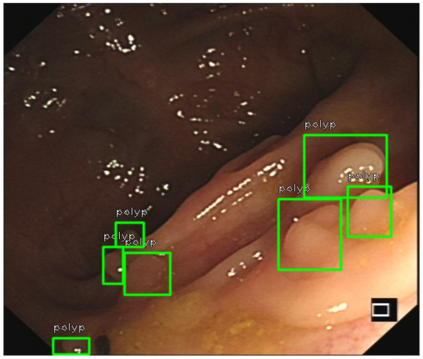

We improved an existing end-to-end polyp detection model with better average precision validated by different data sets with trivial cost on detection speed. Previous work on detecting polyps within colonoscopy \cite{Chen2018} provided an efficient end-to-end solution to alleviate doctor's examination overhead. However, our later experiments found this framework is not as robust as before as the condition of polyp capturing varies. In this work, we conducted several studies on data set, identifying main issues that causes low precision rate in the task of polyp detection. We used an optimized anchor generation methods to get better anchor box shape and more boxes are used for detection as we believe this is necessary for small object detection. A alternative backbone is used to compensate the heavy time cost introduced by dense anchor box regression. With use of the attention gate module, our model can achieve state-of-the-art polyp detection performance while still maintain real-time detection speed.